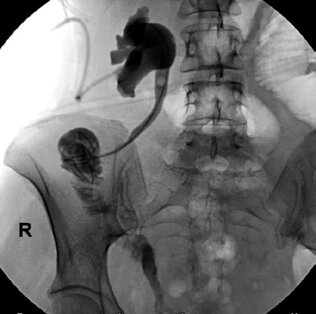

Взятый трансплантат повернут слева направо в изоперистальтическом положении. Излишки кишечных петель в центральной части сегмента резецированы по Ballivet. В бессосудистой зоне брыжейки восходящей ободочной кишки сделано отверстие, через которое трансплантат проведен в область правого бокового канала. На интубаторе и стенте выполнены анастомозы кишечного сегмента с мочеточником и мочевым пузырем «конец в бок». Интубатор вместе с катетером Фолея выведен по уретре наружу. Установлены дренажи в область анастомозов, рана ушита послойно. Осложнений после операции не наблюдалось, рана зажила первичным натяжением. По результатам контрольной антеградной пиелографии установлено, что проходимость мочевых путей не нарушена, контраст свободно проходит по кишечному трансплантату, попадая в мочевой пузырь (рис. 2).

Рис. 2. Антеградная пиелоуретерограмма справа той же больной через 14 дней после операции. Проходимость мочеточника и кишечного трансплантата хорошая